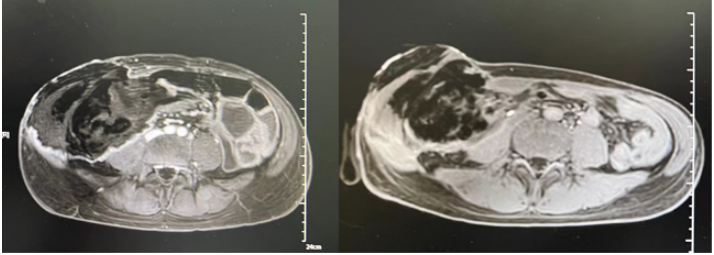

8月25日停用达托霉素,由于当时艾沙康唑暂时不可及,所以使用了两性霉素B胆固醇硫酸酯250 mg/d+亚胺培南抗感染。8月29日腹部MRI平扫+增强+弥散加权成像(DWI):右侧中下腹腔内(以右半结肠为中心)邻近前腹壁-腹膜后巨大边缘环形强化病灶,范围较前稍进展(图7),考虑升结肠缺血坏死,感染较前稍进展,并肠瘘可能。图7 腹部MRI平扫+增强+DWI(2022-08-29)第二次MDT(8月29日):血液科、感染科、普外科、消化科、麻醉科、营养科、临床药学科。MDT意见:患者目前有手术指征,但手术风险极高,预后极差,且费用高昂,继续积极抗感染治疗。患者体温36℃,腹胀腹痛较前稍缓解,可解少量大便,肠梗阻解除,生命体征平稳,转回血液科继续治疗。抗感染:哌拉西林他唑巴坦,两性霉素B胆固醇硫酸酯+艾沙康唑200 mg q8h(第3天开始200 mg qd)。9月2日, 患者体温36.7℃, 全腹胀痛好转, 右下腹皮肤溃烂黑痂, 范围约7 cm×8 cm, 局部破溃渗液(图8)。9月4日晚患者再次出现发热,体温38.3,将哌拉西林他唑巴坦改为亚胺培南+万古霉素抗感染。查血常规:白细胞13.12×109/L,中性粒细胞绝对值11.43×109/L;降钙素原3.57 ng/ml。分泌物细菌(真菌)培养:鲍曼不动杆菌(多重耐药)。9月5日腹部MRI平扫+增强+DWI: 右侧中下腹腔内(以右半结肠为中心)-邻近前腹壁-腹膜后巨大边缘环形强化病灶较前向外膨出、范围较前缩小(图9),考虑升结肠-邻近小肠及腹壁缺血坏死并感染, 肠瘘形成可能, 肠梗阻较前改善。图9 腹部MRI平扫+增强+DWI(2022-09-05)9月9日患者右下腹坏死物膨出,边缘进一步破溃,脱落,暴露腹腔内容物(图10)。在2019年ECMM发布的《毛霉病诊断和管理全球指南》中,指南小组强烈支持,除全身抗真菌治疗外,在可能的情况下,应尽早完成毛霉病的外科治疗。如有需要,应反复行切除或清创术。第三次MDT(9月9日):感染科、普外科、麻醉科、营养科、消化科、烧伤科、ICU、康复科。MDT意见考虑:患者有手术指征,但手术风险极高,需要多学科联合手术同时进行;尽快完善全腹部CT+腹部血管CTA,完善术前高风险谈话及手术/麻醉评估,患者及家属手术意愿强烈可考虑充分术前准备后手术。9月9日腹部CT+腹部血管CTA:肝中动脉瘤;腹主动脉+肠系膜上、下动脉+肾动脉CTA未见异常。9月10日行腹壁坏死组织切除+回肠部分切除+回肠造瘘+肠粘连松解术,术后转ICU观察。术中见:右下腹一13 cm×13 cm坏死腹壁与肠管组织,与周围组织无粘连,予以取出,回盲部、部分乙状结肠、右侧上段输尿管包裹在腹壁坏死组织中(图11)。病理组织活检:骨骼肌及肠壁可见大量真菌菌丝、孢子及细菌菌团,且部分真菌菌丝及孢子似位于脉管内,倾向侵袭性真菌病并广泛播散;见阑尾组织显著急性坏疽性阑尾炎,阑尾管壁及管腔内见真菌菌丝及孢子。9月14日患者生命体征平稳,无发热,为求坏死腹壁修复,转入烧伤科继续治疗。9月15日患者生命体征平稳,胆仍有腹痛、腹胀,转入胃肠外科治疗,后续进食半流质,腹痛缓解,造瘘处有排便排气。术后持续予以两性霉素B胆固醇硫酸酯+艾沙康唑治疗。9月20日腹部增强CT示(图12):“腹壁坏死组织切除+回肠部分切除+回肠造瘘+肠粘连松解术”术后改变,右中下腹术区少量渗出、积液;左侧回肠造瘘口近端小肠积液、积气扩张;右侧输尿管上段继发右肾及输尿管上端轻度积水同前;盆腹腔脓肿较前吸收。肠腔内高密度影,造影剂残留?肝中动脉动脉瘤较前增大。肝脏多发低密度灶同前,仍考虑小脓肿形成可能。9月22日,患者生命体征平稳,复查骨髓形态及流式均未见异常细胞。11月1日,烧伤整形科于全麻下行"右腹壁腹膜补片修补+腹壁缺损右股前外侧皮瓣转移修复术"。术前已停用两性霉素B,予以艾沙康唑口服维持治疗。2024年1月3日随访腹部CT提示患者恢复较好(图13)。